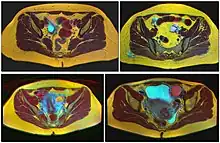

Transvaginal ultrasonography showing a 67 x 40 mm endometrioma, with a somewhat grainy content.